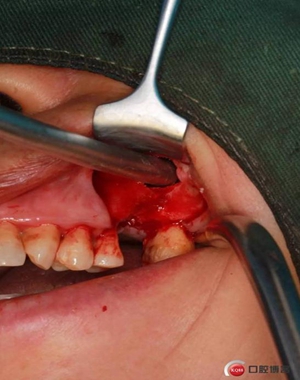

改良式外提升工具盒-外提 科貿(mào)嘉友收錄

大家好,我是梁老師的助理小依。由于梁老師每天手術(shù)檔期安排較滿,加上經(jīng)常出差講課,沒有時(shí)間整理病例 。為了方便大家更及時(shí)的了解梁老師最新手術(shù)動(dòng)態(tài),以后將由我為大家整理并推送梁老師最新經(jīng)典案例。案例文字旁白少,但圖片會(huì)盡量完整展示手術(shù)全過程,供大家學(xué)習(xí)參考。有任何問題,可以留言,梁老師會(huì)親自為大家解答。感謝大家對梁老師的支持和關(guān)注!